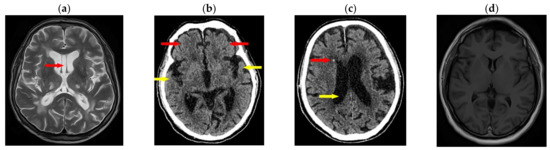

- Jordan, B.D.; Jahre, C.; Hauser, W.A.; Zimmerman, R.D.; Zarrelli, M.; Lipsitz, E.C.; Johnson, V.; Warren, R.F.; Tsairis, P.; Folk, F.S. CT of 338 active professional boxers. Radiology 1992, 185, 509–512. [Google Scholar] [CrossRef] [PubMed]

- Ratajczak, M.; Ptak, M.; Chybowski, L.; Gawdzińska, K.; Będziński, R. Material and Structural Modeling Aspects of Brain Tissue Deformation under Dynamic Loads. Materials 2019, 12, 271. [Google Scholar] [CrossRef] [PubMed]

- Costa, J.M.C.; Fernandes, F.A.O.; Alves de Sousa, R.J. Prediction of subdural haematoma based on a detailed numerical model of the cerebral bridging veins. J. Mech. Behav. Biomed. Mater. 2020, 111, 103976. [Google Scholar] [CrossRef] [PubMed]